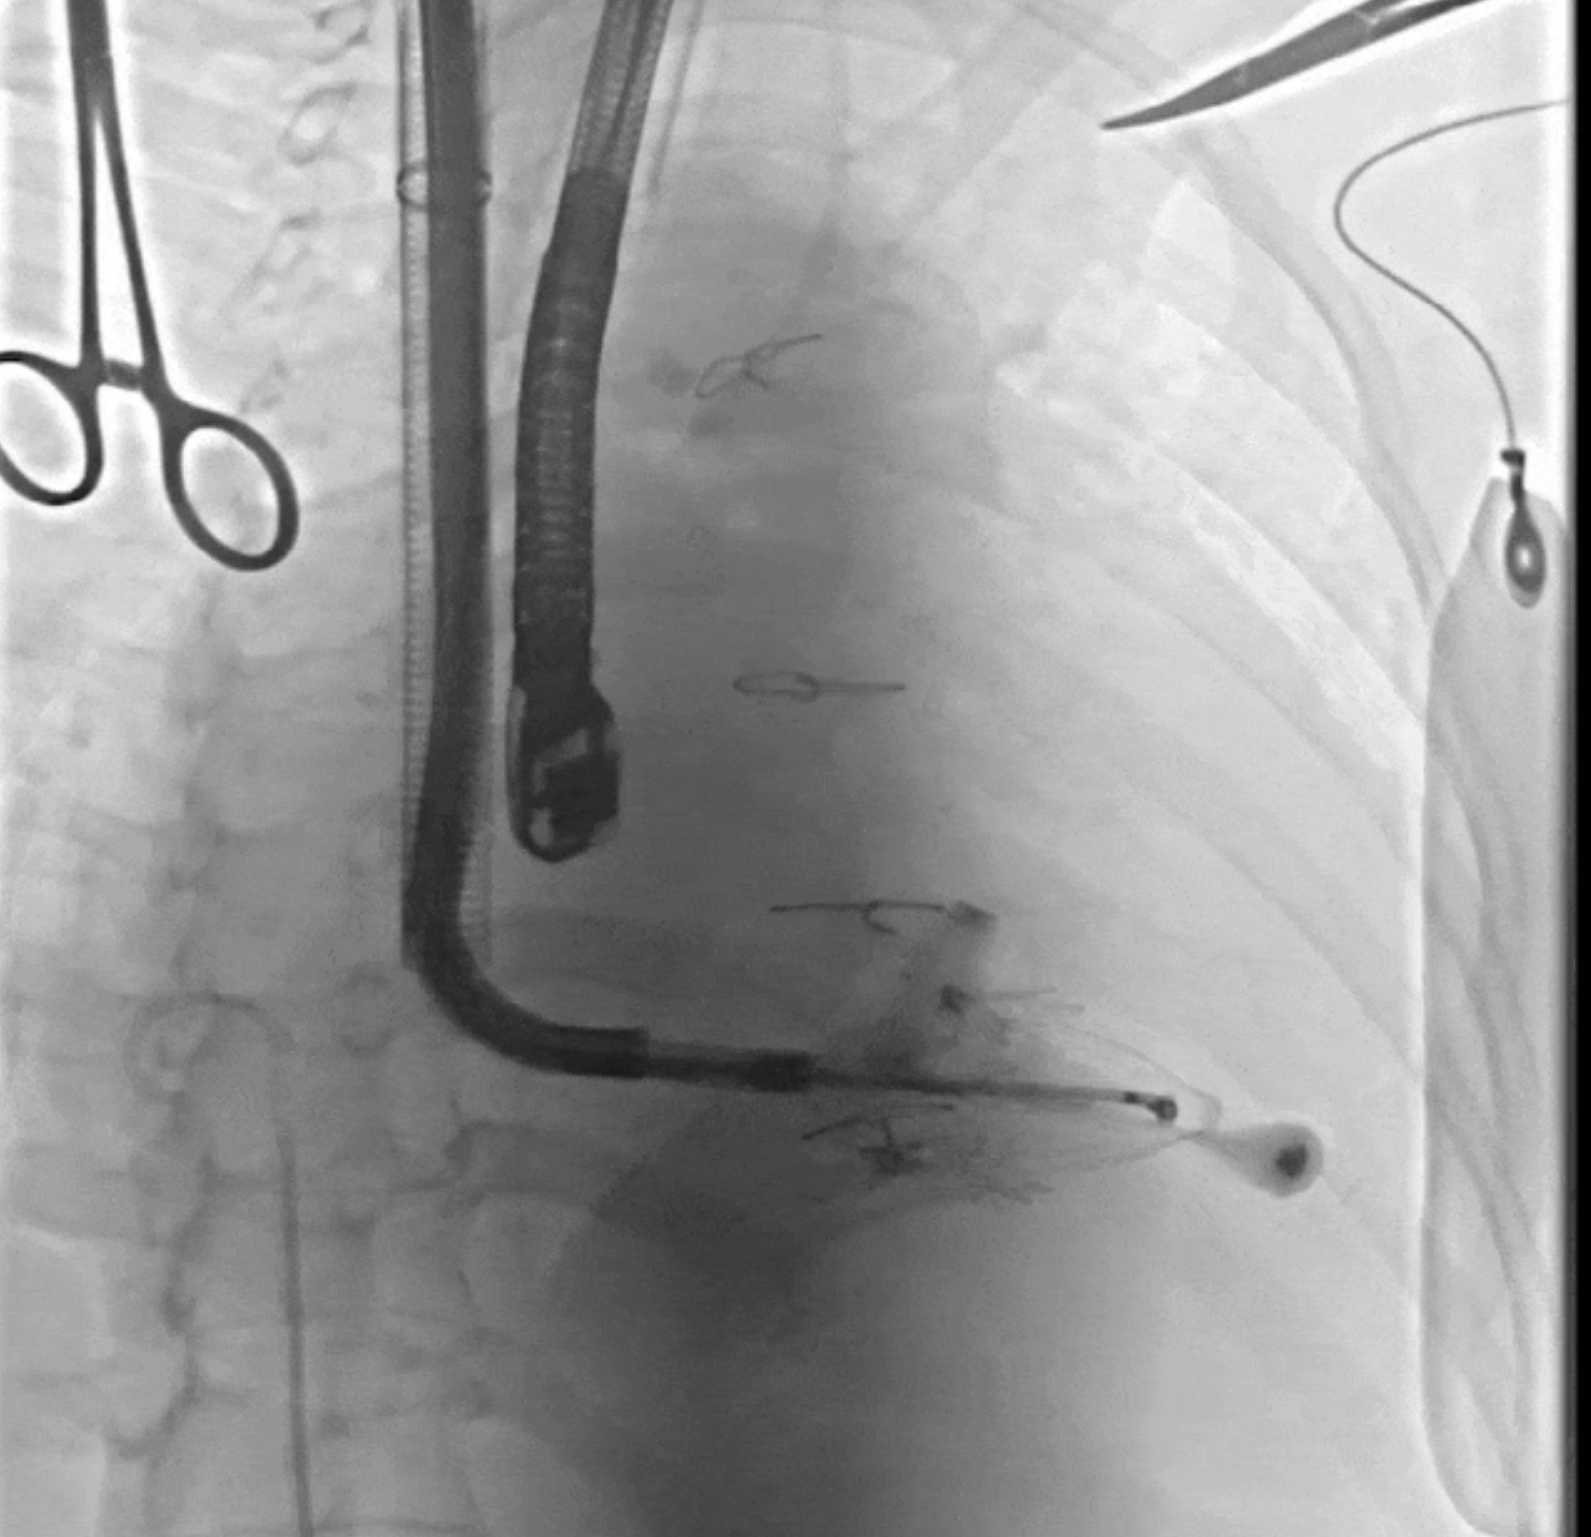

術中DSA所見:經LuX-Valve Plus輸送器系統五向調整,人工瓣膜同軸良好,夾持件均在瓣葉下。